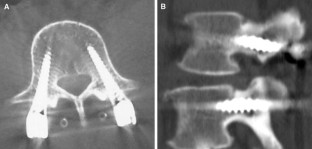

Fig. 1

Fig. 2

Fig. 3

Fig. 4

Fig. 5

Fig. 6

Fig. 7